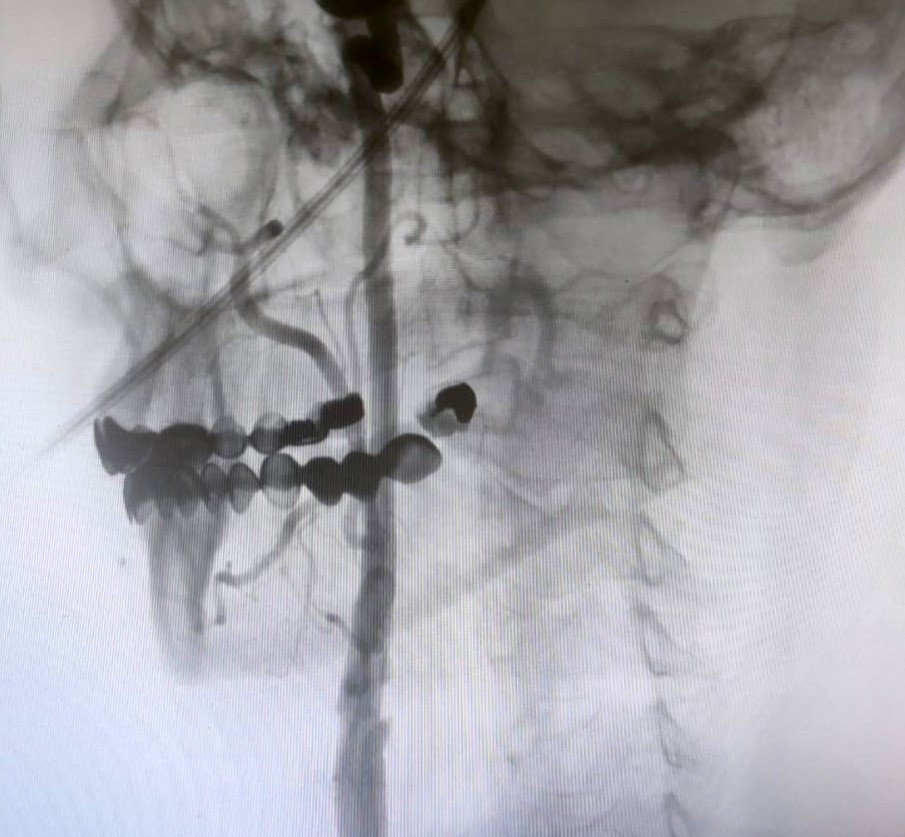

“Boyun damarlarını açma işlemi iki şekilde yapılabilir. Bir karotis endarterektomi dediğimiz ameliyatla bir diğer yöntem ise perkutan girişim dediğimiz stent yöntemiyle açılabilir. Biz kliniğimizde nöroloji ve kardiyoloji olarak bir konsey yapıyoruz. Damarı ciddi tıkalı olan ve buna bağlı felç geçirmiş hastalarda bu konseyde hastaya işlem yapıp yapmama kararı veriyoruz. Verdiğimiz karar çerçevesinde eğer hastaya işlem kararı vermişsek femoral arter dediğimiz kasık arterinden bir şitle 6 ya da 7 F çapında bir şitle ince bir boruyla bu damara giriş yapıyoruz ve boyun damarlarına ulaşıyoruz. Özellikle teller, filtreler ve stentlerle bu damarları açıp hastanın tedavisini gerçekleştiriyoruz. İşlem ameliyatsız olduğu için hastamız ertesi gün rahat bir şekilde problem olmazsa işlemde taburcu olabiliyor bu işlemden sonra. Bu işlemin yapılması için özellikle anjiografinin olduğu girişimsel nöroloji uzmanının ve girişimsel kardiyoloji uzmanının olduğu ve bu konuda yeterli vaka tecrübesine ve deneyime sahip uzmanların olduğu merkezler gerekir. Bunu yapabilmek için belli bir vaka sayısına ulaşmak ve bu konuda tecrübeli olmak gerekiyor. Biz de Manisa Şehir Hastanesi’ndeki girişimsel kardiyoloji ve nöroloji uzmanları olarak bu işlemi kliniğimizde efektif bir şekilde gerçekleştiriyoruz.”